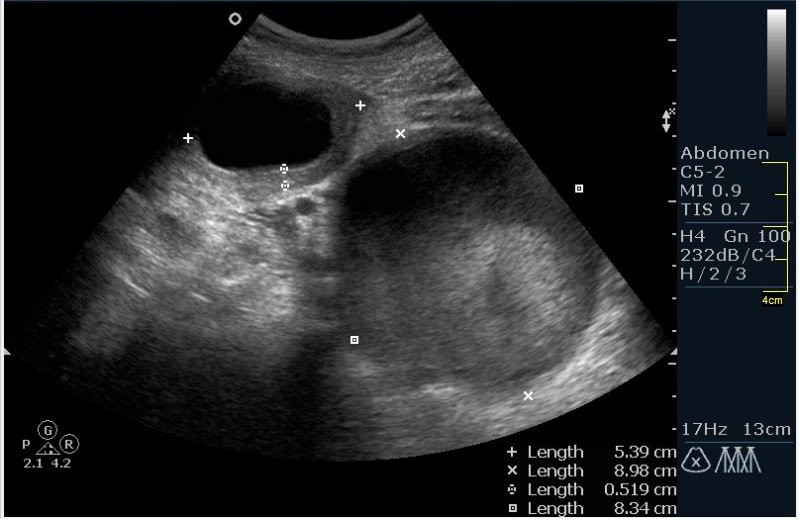

Девочка 12 лет; жалобы на частое мочеиспускание; тупые, тянущие боли в малом тазу. Менструацию отрицает. УЗИ малого таза, все сонограммы выполнены по средней линии, в поперечной и сагитальной проекциях.

Гематокольпос при заращении девственной плевы. Менархе. Врожденная аномалия половых органов.

Согласна с Пасеновым,интересная презентация,поправимый случай.